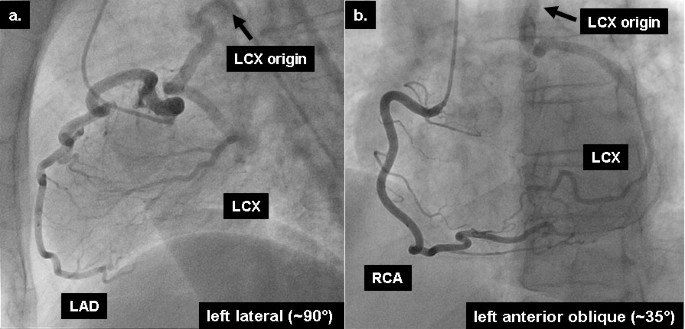

A 54-year-old woman was referred to our institution for routine coronary angiography due to exertional chest discomfort. An exercise ECG by her referring physician was clinically and electrically positive, demonstrating ST-segment depression in leads V5 and V6. Furthermore, nuclear scintigraphy had confirmed the presence of inducible ischemia in the lateral myocardial wall, by showing a reversible perfusion defect in this region during ergometric stress. Coronary angiography showed a normal left anterior descending coronary artery (LAD), while the LCX was filled retrogradely by collateral flow through the LAD (figure 1a). The right coronary artery (RCA) arose in typical position and also provided retrograde filling of the LCX (figure 1b). No evidence of atherosclerotic disease was found, either in the left system or in the RCA, and the origin of the LCX (black arrow) was postulated to be the pulmonary artery. To trace the exact anatomical origin of the anomalous LCX, cardiovascular magnetic resonance (CMR) was performed in a clinical 1.5T scanner (Achieva, Philips Medical Systems, Best, The Netherlands). CMR demonstrated normal function of the left ventricle (ejection fraction of 67%) and no signs of structural heart disease. Multi-planar reformatted images of T1-weighted, free-breathing, whole-heart acquisitions, allowed the unambiguous delineation of the proximal segments of all 3 coronary arteries. Thus, CMR provided the exact anatomical depiction of the origin of the anomalous LCX (solid arrow, figure 2a) from the right pulmonary artery (hatched arrow, figure 2a) and demonstrated the normal origin of the LAD and RCA (figure 2b). The patient was then referred for cardiac surgery.